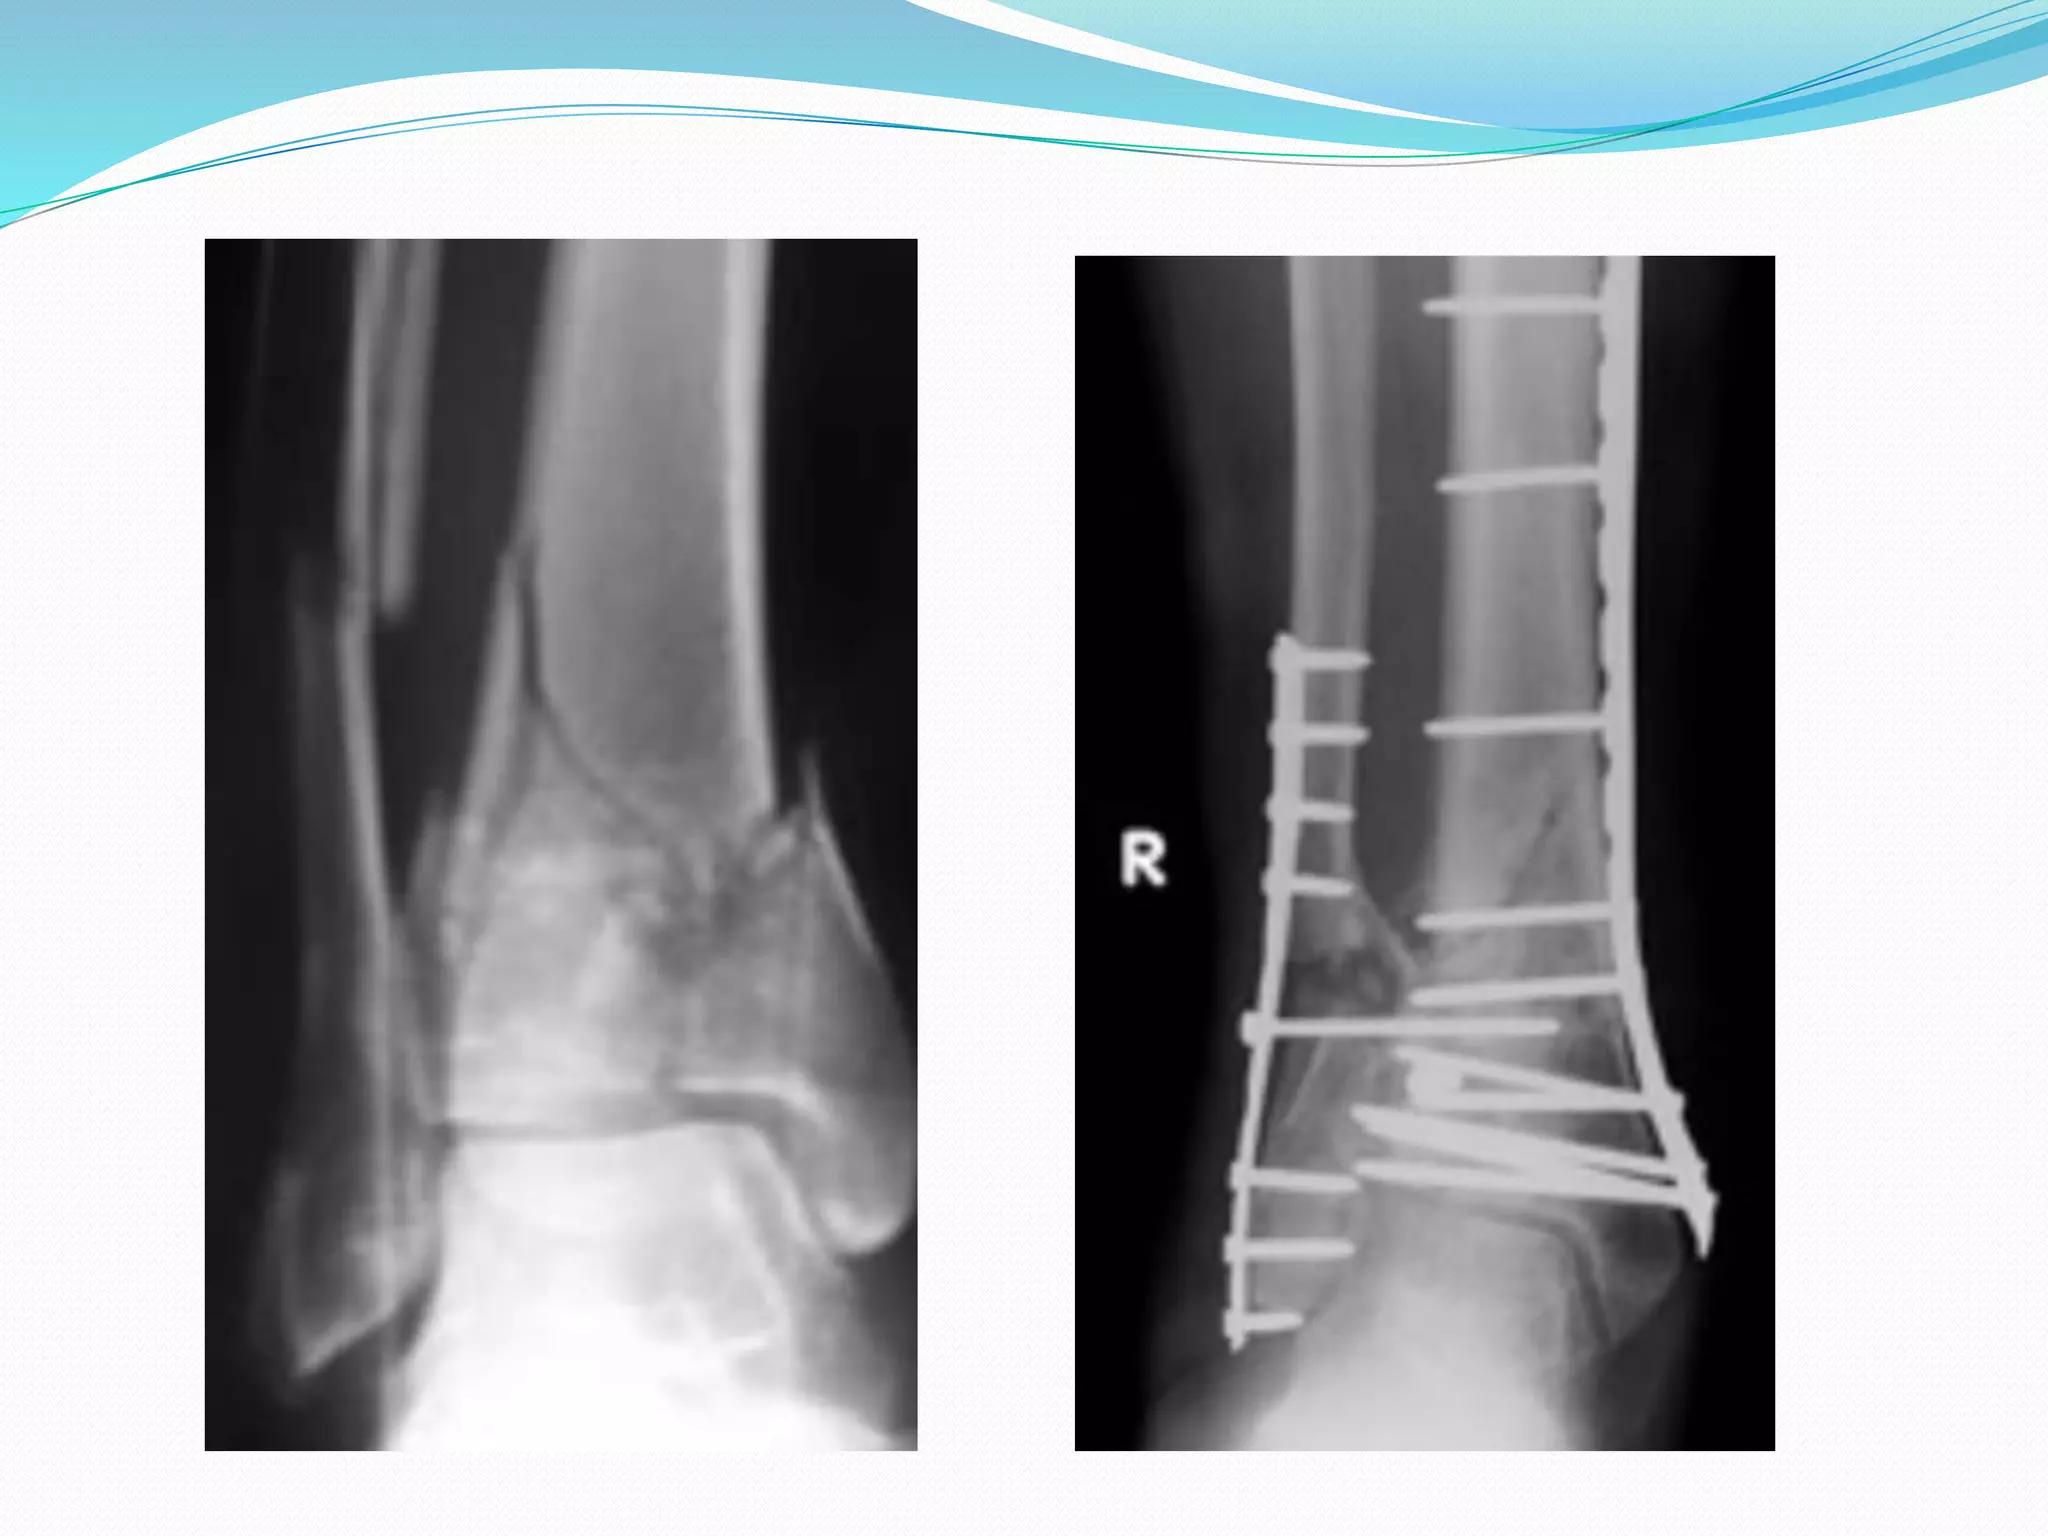

 1. ORIF, Open Reduction Internal ‘‘rigid’’

Fixation

Reudi & Allower …… type 1

AOOTA………………………. A1,A2 ---YES

C-Fractures not advocated